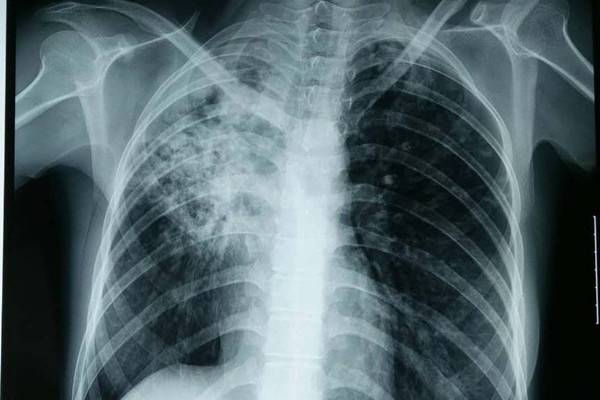

当肺部结核炎症累及胸膜时引起的胸膜炎症称为结核性胸膜炎。在某些情况下胸膜炎是通过血行感染而致病的,也有部分是与机体的变态反应有关。

患上结核性胸膜炎后,其症状主要表现为结核的全身中毒症状和胸腔积液所致的局部症状。结核中毒症状主要表现为发热、畏寒、出汗、乏力、食欲不振、盗汗。局部症状有胸痛、干咳和呼吸困难。胸痛多随深呼吸或咳嗽而加重。当胸腔内积液逐渐增多,几天后胸痛逐渐减轻或消失。大量积液压迫肺、心和纵隔,则可发生呼吸困难。